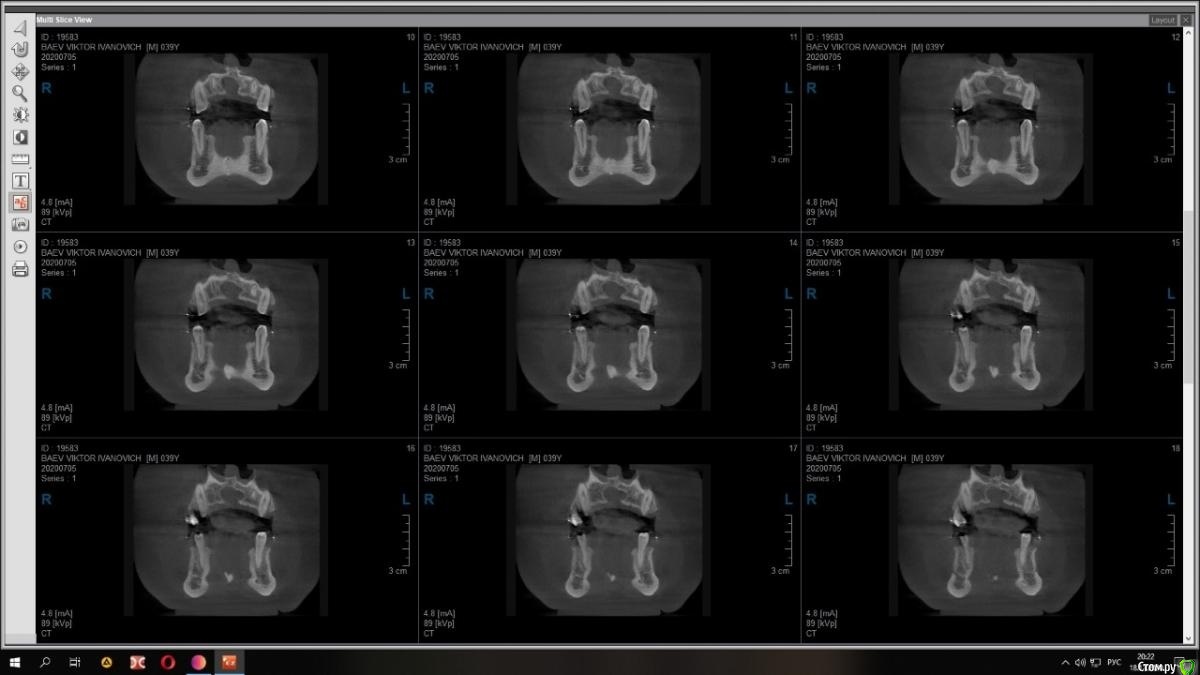

Raystom Опубликовано 15 декабря, 2020 Поделиться Опубликовано 15 декабря, 2020 Случайно на КТ перед имплантацией 36 обнаружили образование. Похоже на кисту резцового канала. Срезы снимка прилагаются.Варианты решения:1. Стационар и ЛОР, т.к. судя по снимку она, на мой взгляд, состоит из 2х частей и есть очень большая вероятность прорастания в носовой ход2. Убирать самостоятельно, но тут возникает очень много вопросов. С нёба доступ самый простой, но потом непонятно как закрыть костный дефект так, чтобы была возможность восстановления кости. При вестибулярном доступе предварительно придется делать эндо 111 с последующей резекцией, но, непонятно, удастся ли его вообще сохранить. Ещё момент, если убрать только обширную часть (нижний компонент), положить резорбируемую мембрану на дно, а аугментат через 2 месяца, дабы не пророс. При этом верхний компонент убрать с помощью ЛОР-эндоскопии.И организационный вопрос, как будет лучше, как и планировалось провести имплантацию 36, дать человеку отдохнуть на новогодних праздниках, а после уже лечение по поводу кисты Ссылка на комментарий

Raystom Опубликовано 18 декабря, 2020 Автор Поделиться Опубликовано 18 декабря, 2020 Срезы из других проекций Ссылка на комментарий

bilal Опубликовано 19 декабря, 2020 Поделиться Опубликовано 19 декабря, 2020 c чего вы решили что киста. как будто расширенный канал просто Ссылка на комментарий

Raystom Опубликовано 21 декабря, 2020 Автор Поделиться Опубликовано 21 декабря, 2020 c чего вы решили что киста. как будто расширенный канал просто ну не, это 80 процентов она Ссылка на комментарий